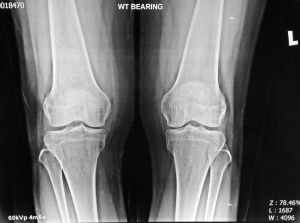

How Does the X-ray Look Like?

In the early stage, the knee x-rays may look normal.

If the x-rays look normal but the pain is severe, always consider a diagnosis of AVN knee.

An MRI scan of the affected knee will be most useful.

In later stages, x rays may show bone damage and collapse.